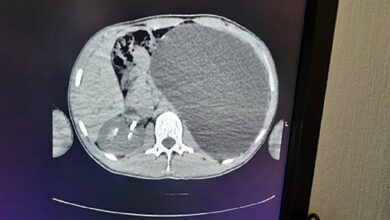

Врачи спасли пациента с почкой размером с пятилитровую бутылку